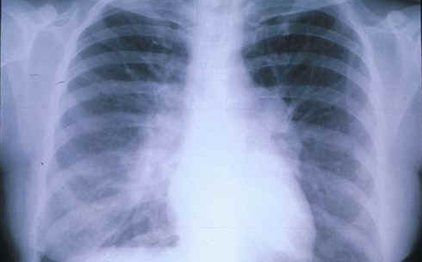

Ελπιδοφόρα μηνύματα για την οριστική νίκη εναντίον του καρκίνου του πνεύμονα. Αμερικανοί ερευνητές επισημαίνουν ότι περισσότεροι από τους μισούς όγκους του πλακώδους καρκινώματος των πνευμόνων, της πιο συνηθισμένης μορφής της νόσου, οφείλονται σε μεταλλάξεις που ελέγχουν την ανάπτυξη των κυττάρων και μπορούν να αντιμετωπισθούν με μια νέα γενιά φαρμάκων, τα οποία ήδη παρασκευάζονται.Ωστόσο, καθώς οι μεταλλάξεις είναι διαφορετικές σε κάθε ασθενή, εξατομικευμένη πρέπει να είναι και η φαρμακευτική αγωγή που χορηγείται.Πηγή: Καθημερινή